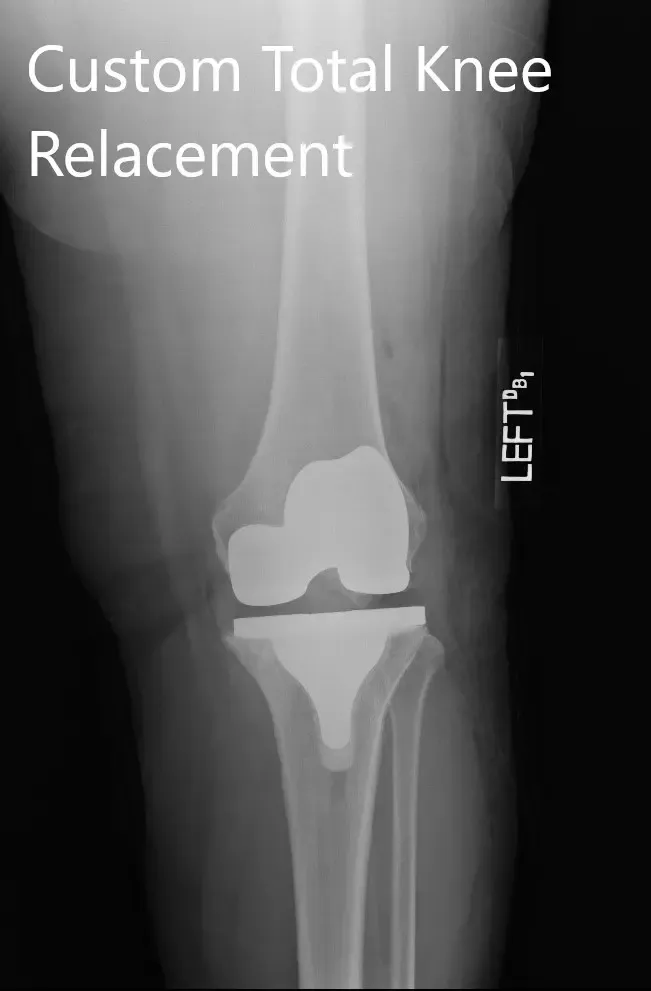

Postoperative X-ray images showing the AP and lateral views of the left knee

Post-op weight-bearing was started on the same day of the surgery. He was able to walk for 50 feet. The pain was well controlled with medications. Aspirin 325mg BID was started for DVT prophylaxis.

The patient demonstrated a full range of motion of the left knee. Physical therapy focusing on muscle strengthening and flexibility was continued. After 2 months, the patient was happily driving his car, performing his daily activities and brought a picture of him playing golf. He follows up as needed.